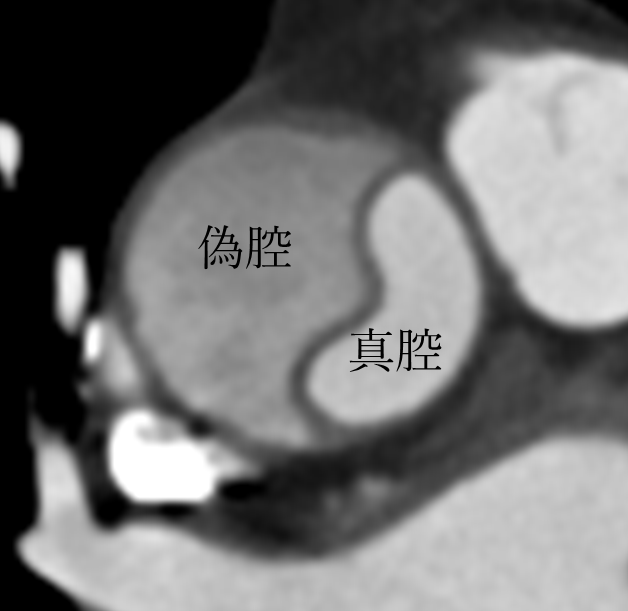

前触れもなく突然発症し、いままで経験したことのない胸痛、背部痛、腰部痛を自覚し、失神する場合もあります。大動脈が解離すると血管内が真腔と偽腔の二つの腔に分かれ(図右)、血管が弱くなって破裂したり、血液の流れが妨げられたりします。